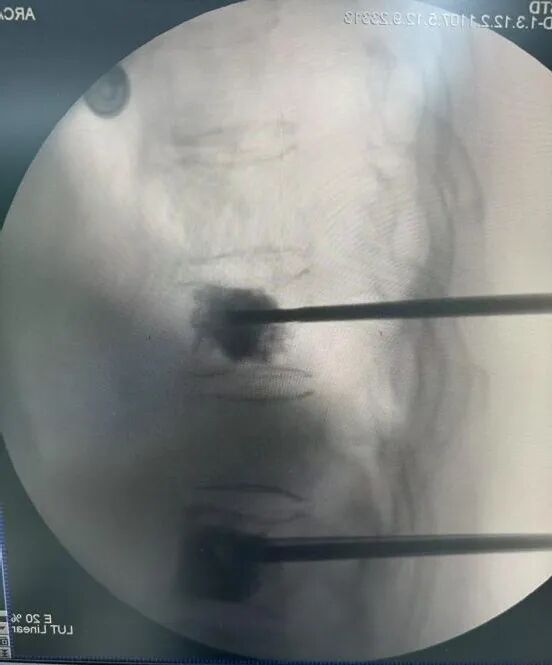

提到脊柱手术,您是否想到的是大开刀、打钢钉、漫长恢复?这个观念过时了。

现在的标准微创治疗叫做“经皮椎体成形术”。医生仅通过一根约2毫米的穿刺针,像打针一样,将一种叫做“骨水泥”的医用材料精准注入骨折的椎体。这个“水泥”能迅速凝固,将被压碎的骨头重新粘合、撑起。患者通常在术后第二天就能戴护具下床行走,效果堪称“立竿见影”。